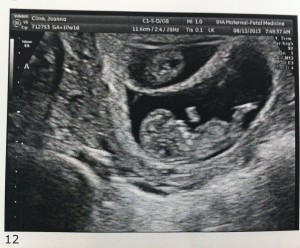

Hello! Today was the all important 12 week ultrasound and everything was great! The fetuses are all measuring about 2.5 inches and their hearts are beating strong. They also like to wiggle around a lot which created some challenges for the very patient ultrasound tech. (With three fetuses to measure, it took about 90 minutes.)